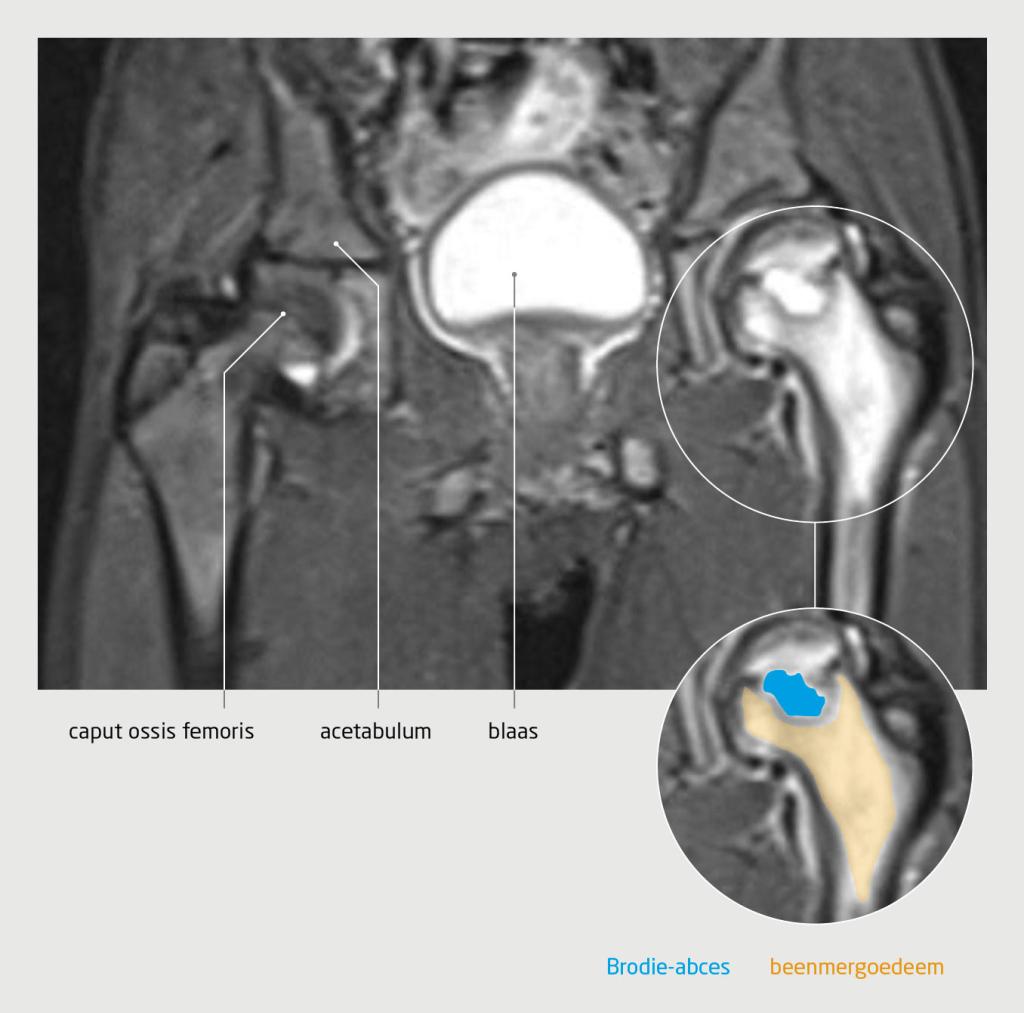

2 weken later bezocht patiënt opnieuw de huisarts, omdat de pijn in het bovenbeen toenam en zich uitbreidde naar de linker heup. Vanwege de aanhoudende pijn en de toename van de klachten verwees de huisarts patiënt door naar de spoedpoli Kinderorthopedie. Aldaar toonde het bloedonderzoek een licht verhoogde bezinking (33 mm na 1 h), zonder verhoging van de overige infectieparameters. Conventionele röntgenopnames van het bekken en het linker bovenbeen lieten geen afwijkingen zien. Wij vermoedden een subacute artritis of osteomyelitis en verrichtten aanvullend een MRI-scan van het bovenbeen en de heup, waarop in het linker proximale femur T2-hyperintense afwijkingen te zien waren, die passen bij een Brodie-abces met omringend beenmergoedeem in het kader van subacute osteomyelitis (figuur 1).

Subacute osteomyelitis bij een jongen van 8 jaar door een infectie met Kingella kingae

Figuur 1 | Subacute osteomyelitis bij een jongen van 8 jaar door een infectie met Kingella kingae

Coronale beelden van de MRI-scan van beide heupgewrichten laten T2-hyperintense afwijkingen zien in het linker proximale femur, die passen bij een Brodie-abces met omringend beenmergoedeem in het kader van subacute osteomyelitis.